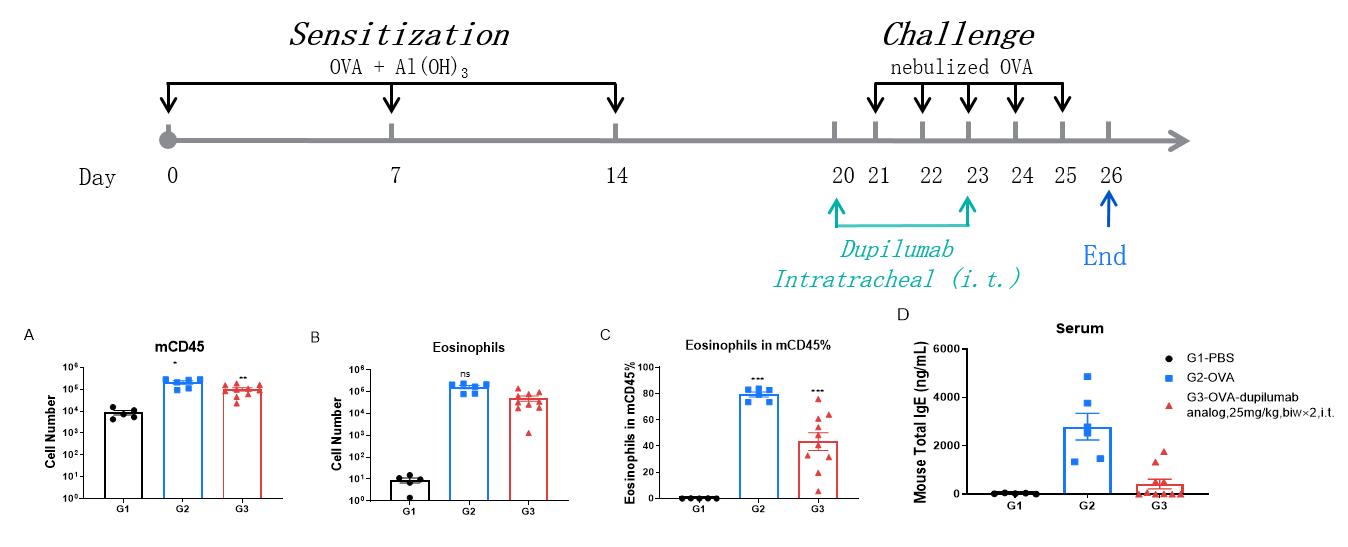

Analysis of immune cells in BALF by FACS and IgE production in serum. BALF immune cells were isolated from B-hIL4/hIL4RA mice. The number and proportion of eosinophils were analyzed by flow cytometry under the treatment of PBS/dupilumab (in house). After treatment of dupilumab (in house), the number of CD45+ cells and eosinophils were much lower than the positive control in homozygous B-hIL4/hIL4RA mice. Serum was collected at the study endpoint. IgE levels were analyzed. The results show that the levels of IgE in mice treated with dupilumab (in house) is much lower than that in untreated mice.

Efficacy Evaluation of the anti-human IL4RA (dupilumab) (in house) in HDM-induced Asthma Model of B-hIL4/hIL4RA mice. (A) The number of CD45+ cells in BALF. (B) The number of eosinophils in BALF. (C) The proportion of eosinophils to CD45+ cells. The results showed that after challenge with HDM, the leukocyte infiltration of mice in G4 model group was significantly increased compared with G3 control group, and their eosinophil content was significantly increased, suggesting that the model was successfully established. After administration of 25 mg/kg dupilumab (in house), the numbers of CD45+ cells and eosinophils were significantly lower compared with the G3 model group. (D) Serum was taken at the end of the experiment and total IgE levels were measured. The results showed that the levels of total IgE in G4 model group were significantly increased compared with G3 control group, suggesting successful modeling. Total IgE levels were significantly lower after administration of dupilumab (in house) drug compared with the G4 model group.